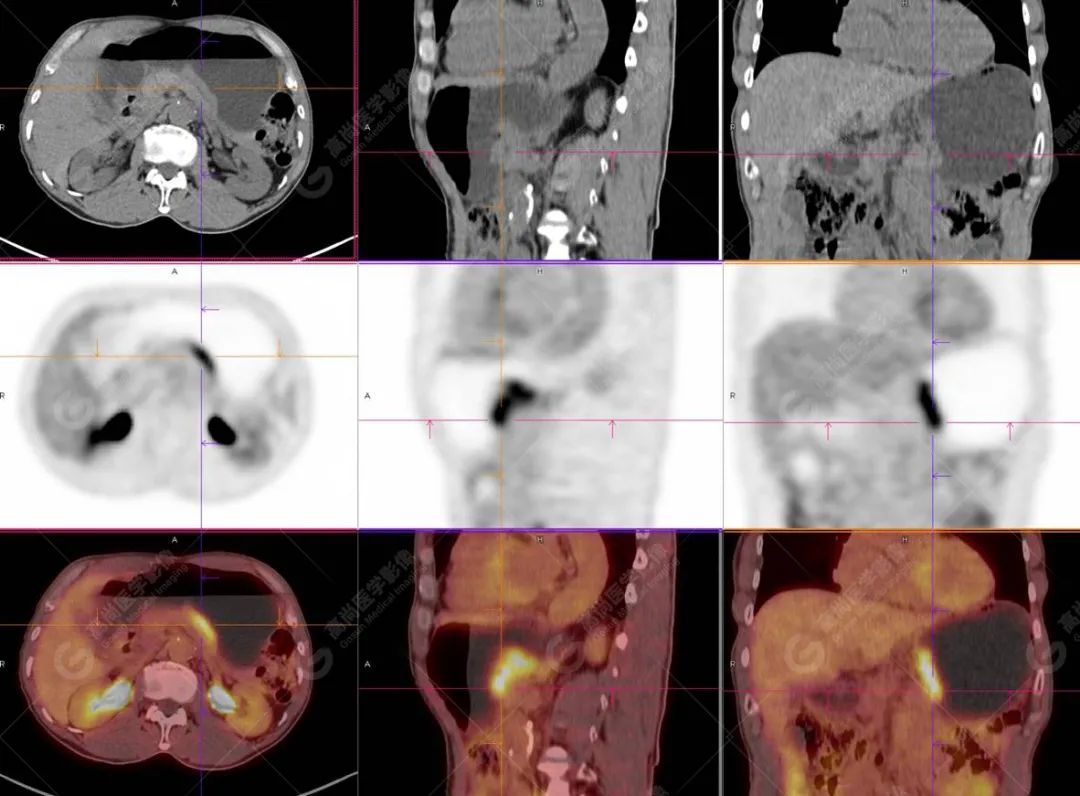

HAS 的影像学表现具有一定特征。CT 上多表现为胃壁不规则明显增厚,平均厚度超过 3.0 cm,肿瘤多向腔内生长形成较大的软组织肿块,易合并出血、坏死,密度不均匀,边界不清晰,常向周围浸润,累及肝脏、胰腺、食管等邻近器官,增强扫描呈轻至中度不均匀强化;腹腔淋巴结转移和肝脏转移常见,肝转移瘤以多发较大的低密度肿块为主,与原发性肝癌(HCC)动态增强扫描方式相似,均呈「快进快出」;易侵犯局部血管,较常见到大的分支如门静脉或脾静脉癌栓形成。

病灶组织的分化程度反映的是恶性程度情况,病灶分化程度越低提示恶性程度越高,对营养物质的需求更高,更容易累及周围组织或器官,再者恶性程度越高的组织,18F-FDG 摄取的越多,PET/CT 代谢参数 (SUV max ) 随之升高明显。

综上所述,HAS 好发于中老年男性,典型表现为胃窦或胃体小弯侧偏心性厚壁肿块,常伴血清 AFP 指标升高且早期易出现胃周淋巴结和肝脏转移。影像学表现符合胃癌且临床伴有血清 AFP 指标明显升高的患者需要考虑到 HAS 的可能。当发生肝转移时与原发性肝癌的主要鉴别点为是否有肝炎及肝硬化病史。